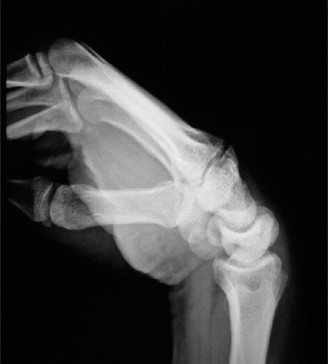

The correct answer is (B). The patient has a severe SLAC wrist with involvement of the midcarpal joint. Loss of cartilage over the proximal pole of the capitate precludes a proximal row carpectomy. By the same token, interposition arthroplasty at the radio carpal joint alone fails to address the midcarpal problem. The use of a silastic prosthesis for the scaphoid has been abandoned due to very high rates of failure. Objectives: Did you learn...? Properly perform the Watson’s test? Identify a SLAC wrist and treat it? CASE 13 ### A patient presents with a history of chronic wrist pain of 6 years duration. He stated that he sustained a fall 9 years ago. Immediately after injury, he did not seek any medical attention, thinking that he had merely sprained his wrist. An xray taken at this visit is shown (Fig. 3–12). What does he have?

Figure 3–12(©) Sunil Thirkannad and Christine M. Kleinert.

The correct answer is (A).

- Scaphoid nonunion with advanced collapse

The correct answer is (E). Any of the above-mentioned procedures can be considered for a patient with SNAC wrist. The specific procedure chosen depends on the amount of midcarpal and radio carpal (especially radiolunate) involvement, as well as the patient’s level of physical activity participation.